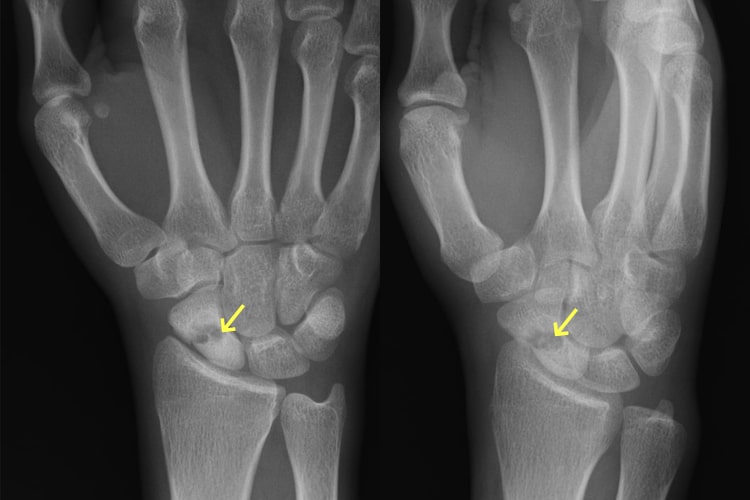

舟状骨骨折写真

舟状骨骨折後偽関節

舟状骨骨折術後写真

骨移植併用内固定術後

原因

スポーツや事故で手をついて転倒することで生じます。舟状骨骨折は通常のレントゲン写真で分かりづらいことも多く、専門医でないと見落とすこともあります。手首の痛みが残る場合は舟状骨骨折を疑って多くの方向からレントゲン写真を撮ったり、CT撮影をする必要があります。

症状

腫れや痛みなどの症状が軽いため、整形外科への受診が遅れたり、手首の捻挫や打撲として診断されてしまっていることがあります。

治療方針

直後で骨折部のズレが少なければギプスで治療することも可能です。しかし、骨折部のズレが大きければ手術となります。また、長期間放置されて骨折部が治らないままとなったり(偽関節)、それに伴って関節の軟骨が摩耗した場合(変形性手関節症)は侵襲の大きな手術が必要となります。